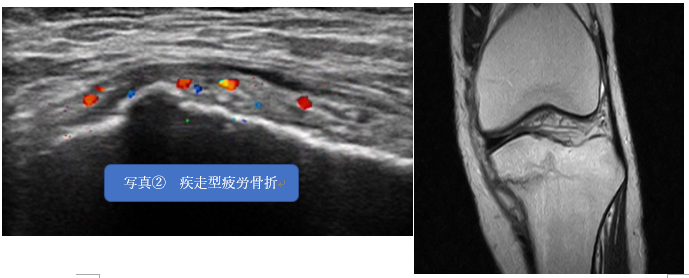

ちなみに写真②は疾走型疲労骨折です。

こちらは一か月程度の安静で治癒に至ります。